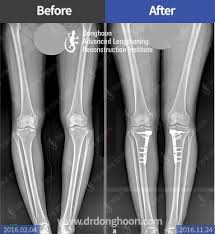

– Sau 4 ngày bạn được chụp phim kiểm tra.

– Sau 18 tháng – 24 tháng có thể tháo bỏ nẹp vít nếu bạn có nhu cầu. Nếu không có nhu cầu, nẹp vit này có thể để vĩnh viên trong cơ thể mà không ảnh hưởng gì tới sức khỏe, do chất liệu nẹp dùng là nẹp Titan, đảm bảo đủ tiêu chuẩn châu Âu.